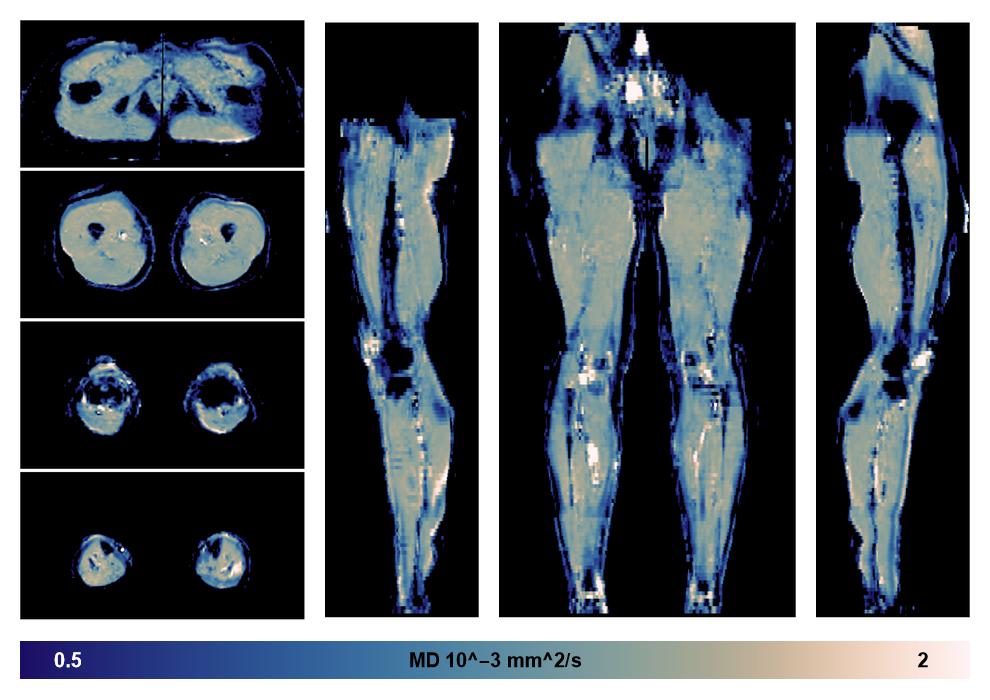

• Mean diffusivity

IVIM corrected whole leg muscle mean diffusivity obtained from diffusion tensor imaging.